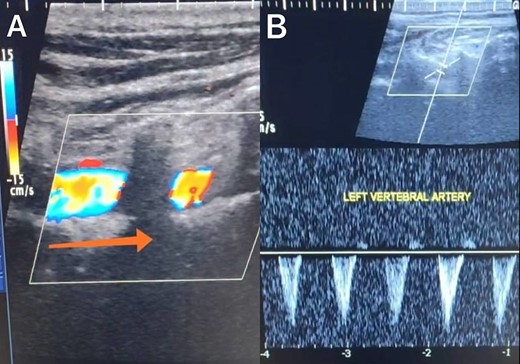

A 65-year-old male presented with recurrent transient ischemic attacks (TIAs), characterized by severe balance disturbances, transient alterations in consciousness, and visual obscurations. Clinical examination revealed high blood pressure in the right arm and absent left radial and brachial artery pulses. Vital signs were normal. Laboratory tests are analyzed as follows: urea: 22 mg/dl, glucose: 150 mg/dl, cholesterol: 199 mg/dl, and triglycerides: 222 mg/dl. A medical history of type 2 diabetes mellitus (DT2), hypertension (HTN), hyperlipidemia, ischemic heart disease, and a heavy smoking history were recorded. Five years before presentation, the patient underwent coronary stenting. Medication history included metformin 1000 mg, aspirin 81 mg, rosuvastatin 40 mg, and ramipril 5 mg. Neck duplex ultrasound (DU) showed normal flow direction and insignificant atherosclerotic plaques in the left internal carotid artery (CA) and left external CA (Figs 1 and 2), normal common CA (Fig. 3), a completely inverted flow direction in the left VA (Fig. 4) that suspected a significant ostial lesion in the left SCA. Multi-slice computed tomography angiography demonstrated 99% stenosis at the left SCA origin and confirmed the presence of SSS (Fig. 5). A balloon angioplasty was unsuccessfully attempted to expand the left SCA. A left carotid VA bypass surgery was performed, and a vascular graft was used to establish a blood flow pathway between the left VA and the left CA. By follow-up, the patient was stable without complications.

Duplex ultrasound showing a normal flow direction in the common carotid artery.